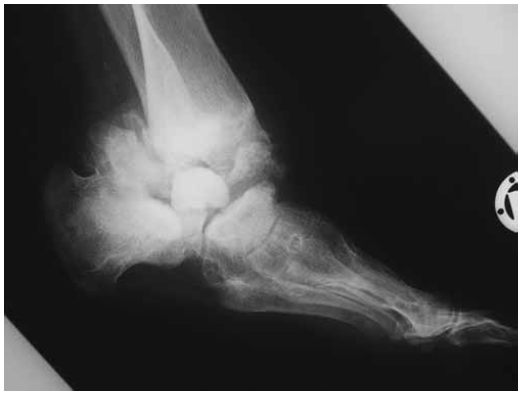

The patient is a 13-year-old girl with complete insensitivity to pain. She is the product of the first pregnancy of a non-consanguineous Austrian couple. At birth her weight, length and head circumference were around the 75th percentile. Family history was unremarkable. The prenatal and postnatal history of the child was normal. At the age of 9-years she went skiing for which she developed ankle joint fracture without pain. Primarily, it was not diagnosed as a pathological fracture. She underwent a series of vigorous investigations. Complete blood count, erythrocyte sedimentation rate, blood electrolytes, calcium, phosphate, alkaline phosphatase and blood sugar were normal. Liver, kidney, and thyroid function tests were normal. Clinical examination showed a normal-looking girl with no specific dysmorphic features. Neurological examination showed no response to pain, but normal responses to touch and temperature as well as normal tendon reflexes. Muscle power was normal. The results of electromyographic and nerve-conduction studies were normal. Abdominal and renal ultrasounds were normal. On the bases of skeletal survey, a Charcot ankle joint was identified. Anteroposterior ankle radiograph with 3/4 foot showed Charcot changes more marked over the left joint with multiple loose bodies. Amortise view of the ankle showed accumulated trauma associated with progressive lytic changes was the reason to develop severe Charcot joint. Dislocation, fragmentations and avascular necrosis were evident (fig. 1). lateral view of the ankle showed accumulated trauma associated with progressive lytic changes was the reason to develop severe Charcot joint. Dislocation, fragmentations and avascular necrosis were evident (fig. 2) Lateral ankle joint radiograph showed advanced stage of Charcot joint with disastrous destruction of the ankle joint associated with extensive callus formation and complete distortion of the joint shape (fig. 3). At this stage, we discussed the treatment options with the parents and the girl. Amputation was an option, which was totally rejected by the family. Then, we decided to perform surgical correction. All the pathologic tissue of the ankle joint was resected and the distal tibia and the calcaneus were fixed together by using Ilizarov frame. Tibial-calcaneal fusion turned out to be successful and 6 months later we were able to remove the external fixator. The girl became able to walk with the aid of special shoes.

Fig. 1. Amortise view of the ankle joint showed Charcot changes with severe involvement of the left joint with multiple loose bodies. However, lytic changes/resorption of the proximal and the distal phalanges, joint space narrowing and avascular necrosis were evident on both joints